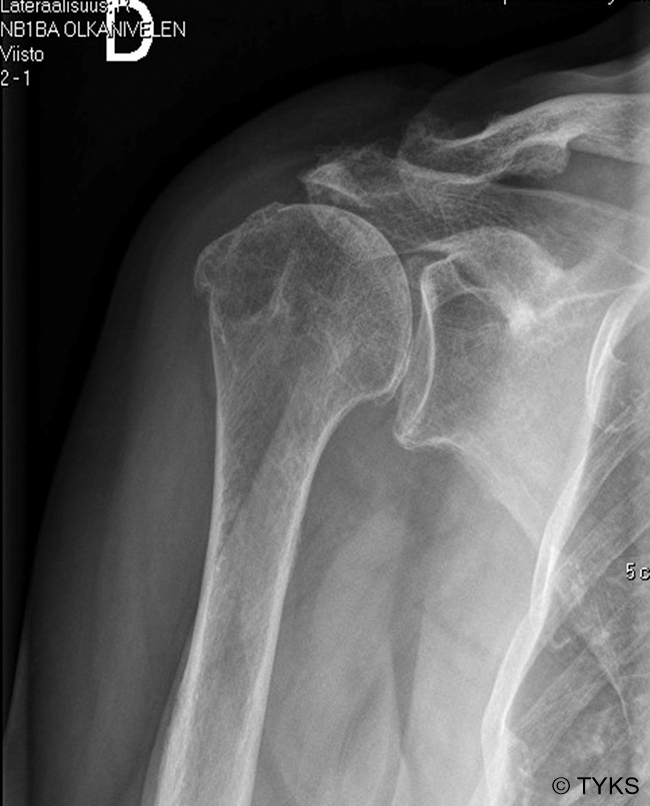

Rotator Cuff Arthropathy on Shoulder x-Ray

Rotator cuff arthropathy on shoulder x-ray. A high riding humerus and decreased subacromial space associated with rotator cuff arthropathy.

Picture: Turku University Hospital, text: Juha Kukkonen, Kaisa Lehtimäki and Anssi Ryösä